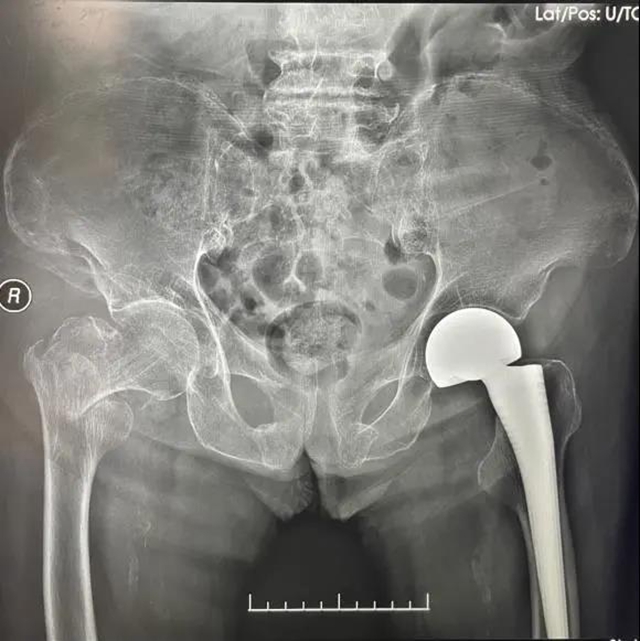

第一次手术,术后X片检查

骨与关节外科后立即采用多学科协作模式(MDT),综合评估与讨论患者情况,采用ERAS(加速康复外科)理念,经过快速缜密充分的术前准备,于入院48小时内,由谭美云教授为患者施行左侧人工股骨头置换手术,手术过程顺利,手术时间约为30分钟,术中出血量约为50ml左右。

术后,继续采用ERAS加速康复理念,积极处理与预防术后并发症,充分镇痛,增加身体协调能力和自理能力,实现早期下床。

术后当天,何婆婆可以自行进食,第2天即开始扶助行器下地练习行走,于术后第6天顺利出院。出院后何婆婆已经能够完全行走,日常生活基本自理,家属对治疗效果十分满意。